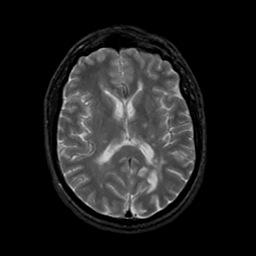

MR Study #19, August 25, 1991 -- Slice #28